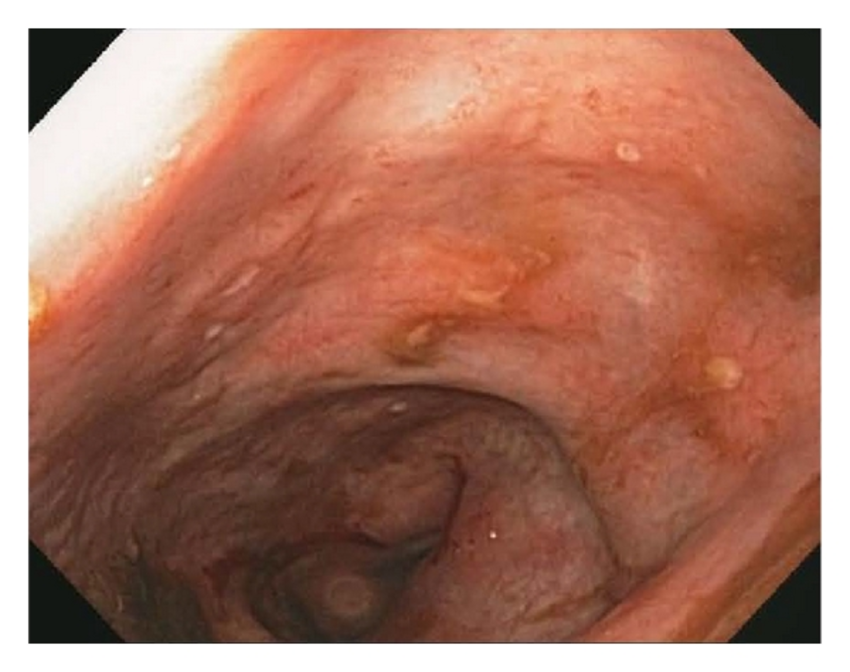

Based on these haemato-instrumental data, endoscopic examinations (gastroscopy and colonoscopy) are performed and the determination of calprotectin (tested positive with a value of 72 g/kg). The typical lesions found at the colonoscopy first and at the histology of the colic mucosa biopsy later, allowed Crohn's disease to be diagnosed.

This clinical case is intended to illustrate how the definitive diagnosis is often obtained after a long period punctuated by complications, which can be misleading. In this patient, the cause of the origin of the numerous infections, microcytic and sideropenic anaemia, spondylodiscitis and numerous pneumonias is ultimately attributed to a chronic inflammatory disease, Crohn's disease: the ulcerated colic lesions are the site of the origin of the septic foci.

Endoscopic features of Crohn’s disease. Photo credits5